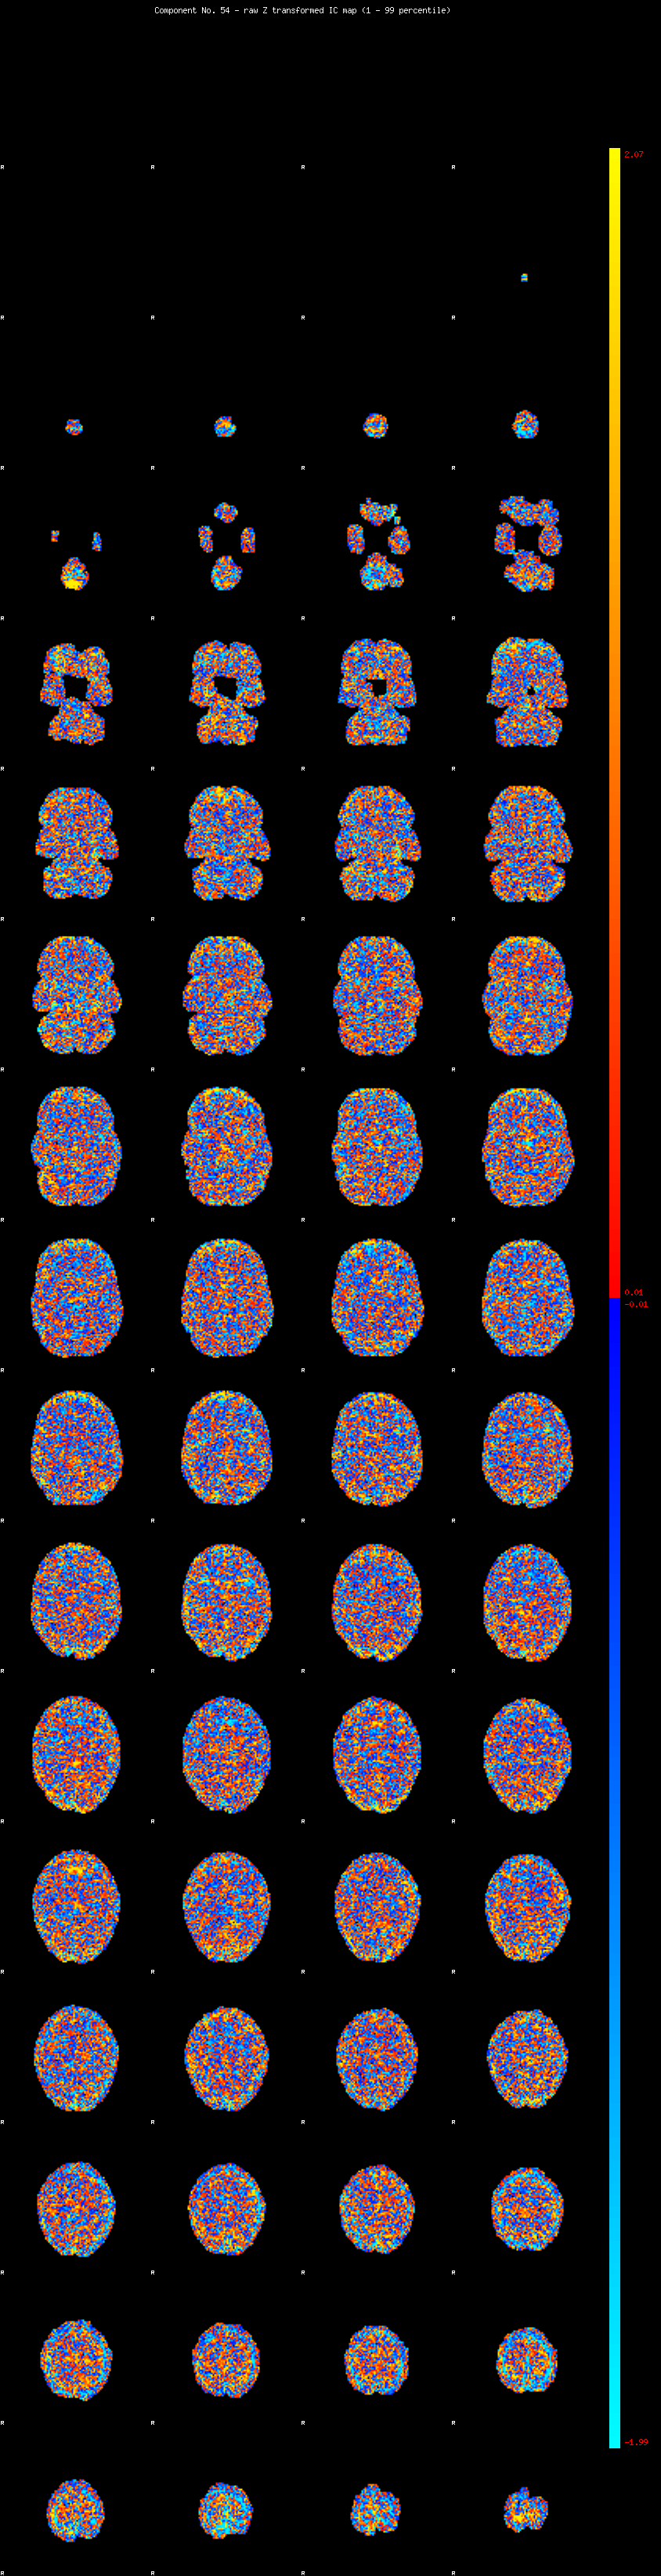

IC_54 Mixture Model fit

Means : -0.000000 2.078249 -2.066718

Vars : 1.000000 0.786181 0.774674

Prop. : 0.904180 0.053058 0.042762